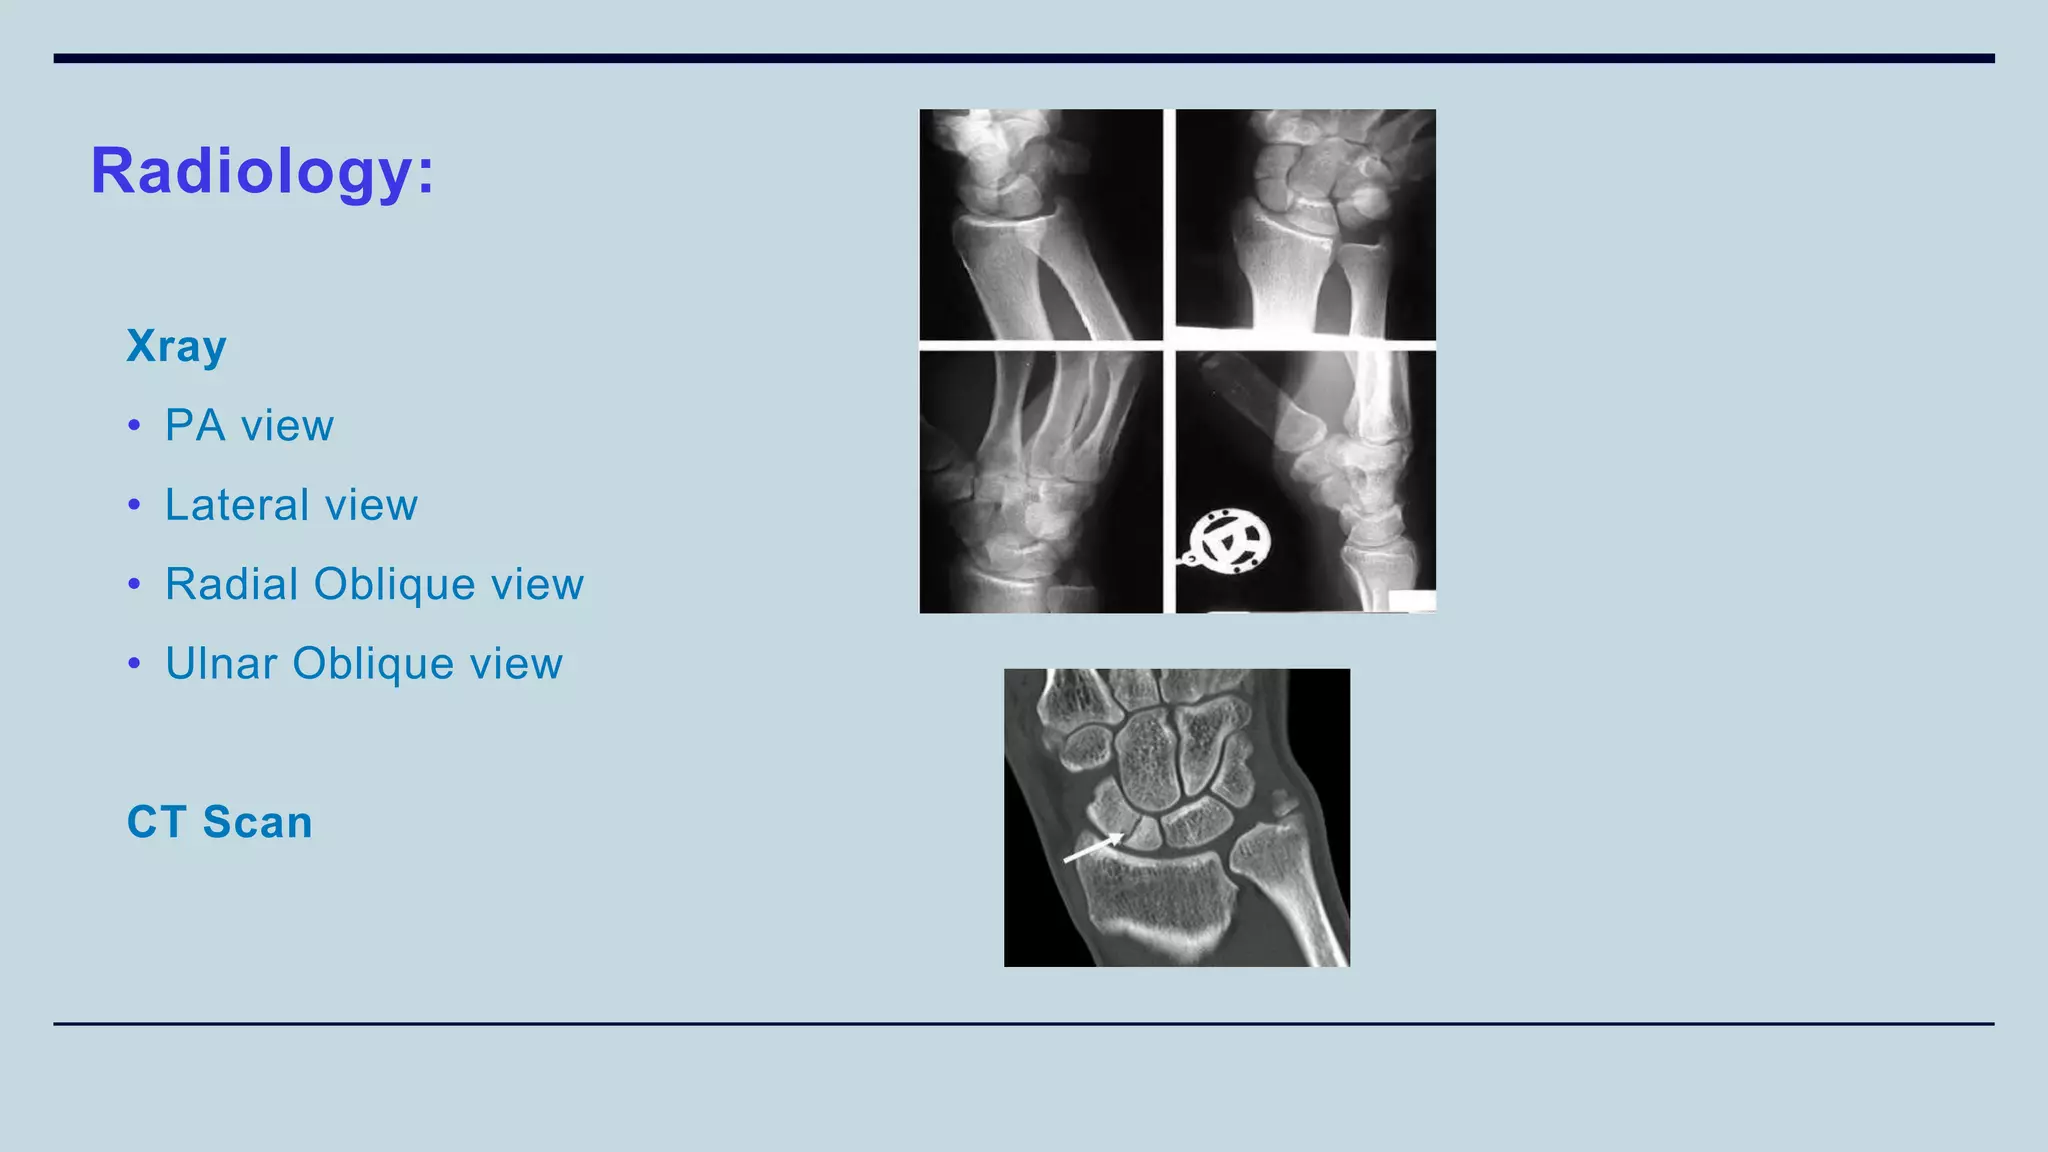

Xray

• PA view

• Lateral view

• Radial Oblique view

• Ulnar Oblique view

CT Scan

Radiology: